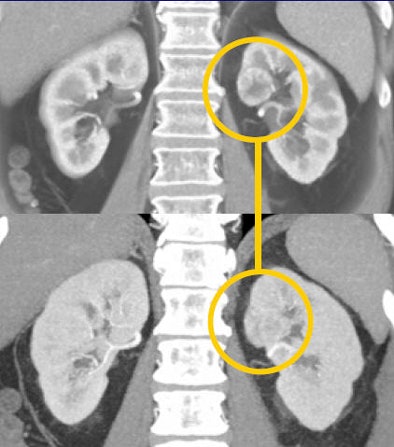

CT images from a patient with transitional cell carcinoma (TCC) were also best appreciated in late-phase imaging. The early-phase data showed slight differential diffusion between the right and left kidneys and a subtle lower-density region in the right kidney. With excretory-phase imaging, the TCC was visible in the axial view and was even more clearly defined in the coronal view.

![]() |

| In a patient with TCC, slight perfusion differences can be seen between the right and left kidneys in the arterial phase (above), and a subtle lower-density zone can be appreciated in the right kidney. On excretory-phase imaging, in both the axial view (below) and coronal view (bottom) it becomes an obvious infiltrative tumor. |